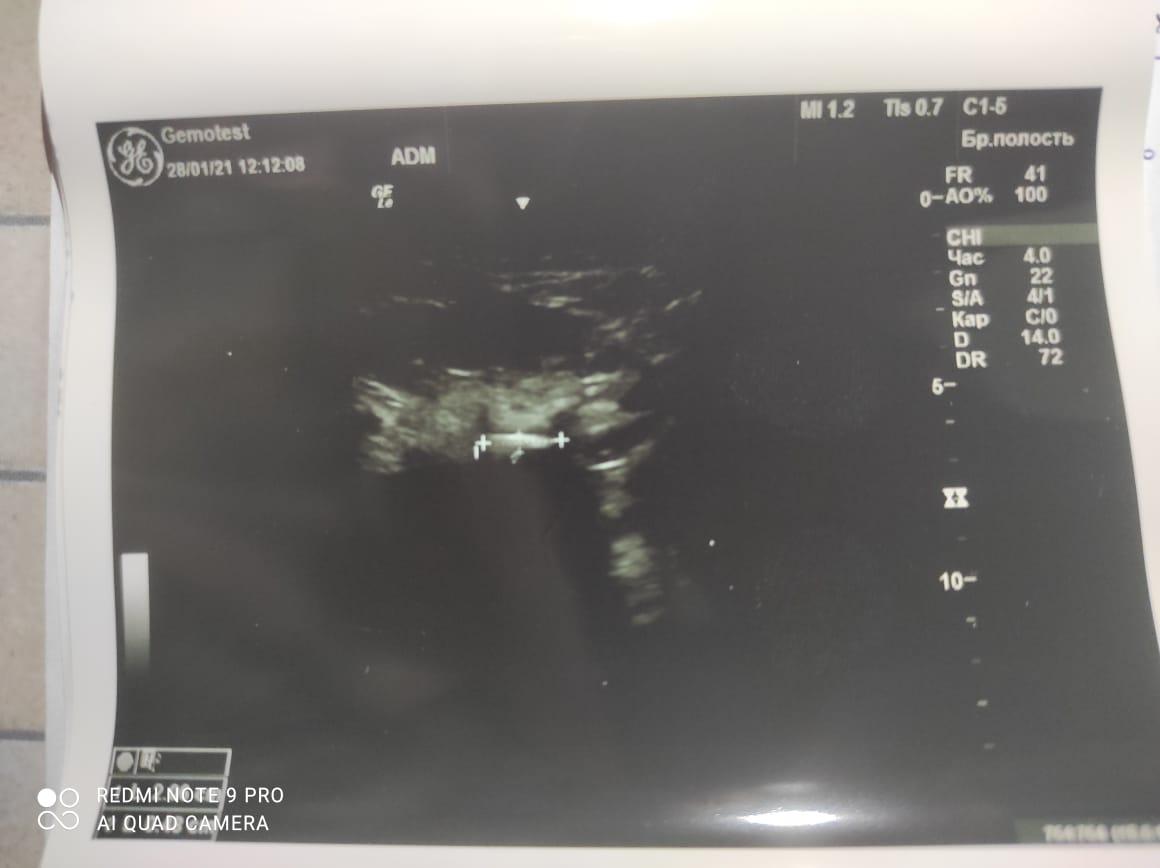

Здравствуйте! При наличии коралловидного камня правой почки(заключение УЗИ), можно предположить причиной боли нарушение уродинамики верхних мочевых путей), что, однако, не подтверждается результатами УЗИ почек( ЧЛС не расширена). Другая, наиболее вероятная возможная причина "боли в боку" - может быть патология опорнодвигательного аппарата. Необходимо проконсультироваться с неврологом и урологом очно, и согласовать возможность применения противовоспалительных, обезболивающих и спазмолитических препаратов - как первый шаг. В дальнейшем необходимо планировать возможное дальнейшее обследование и лечение. Удачи!